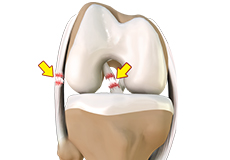

Meniscal Tears

A meniscal tear is a common knee injury in athletes, especially those involved in contact sports. A sudden bend or twist in your knee causes the meniscus to tear. Elderly people are more prone to degenerative meniscal tears as the cartilage wears out and weakens with age.

Meniscal Injuries

Meniscal tears are one of the most common injuries to the knee joint. It can occur at any age but are more common in athletes involved in contact sports. The meniscus has no direct blood supply and for that reason, when there is an injury to the meniscus, healing is difficult.

Lateral Meniscus Syndrome

Lateral meniscus syndrome is characterized by an injury caused by the tearing of the cartilage tissue or a rare case of a congenital abnormality called a discoid meniscus, which results in knee pain.

Medial Meniscus Syndrome

Of the menisci within the knee, it is the medial that is more easily injured. Differences in the anatomical attachments of the medial meniscus compared to the lateral, mean that the medial meniscus becomes distorted during combined flexion and rotation movements in a manner not experienced on the lateral side.